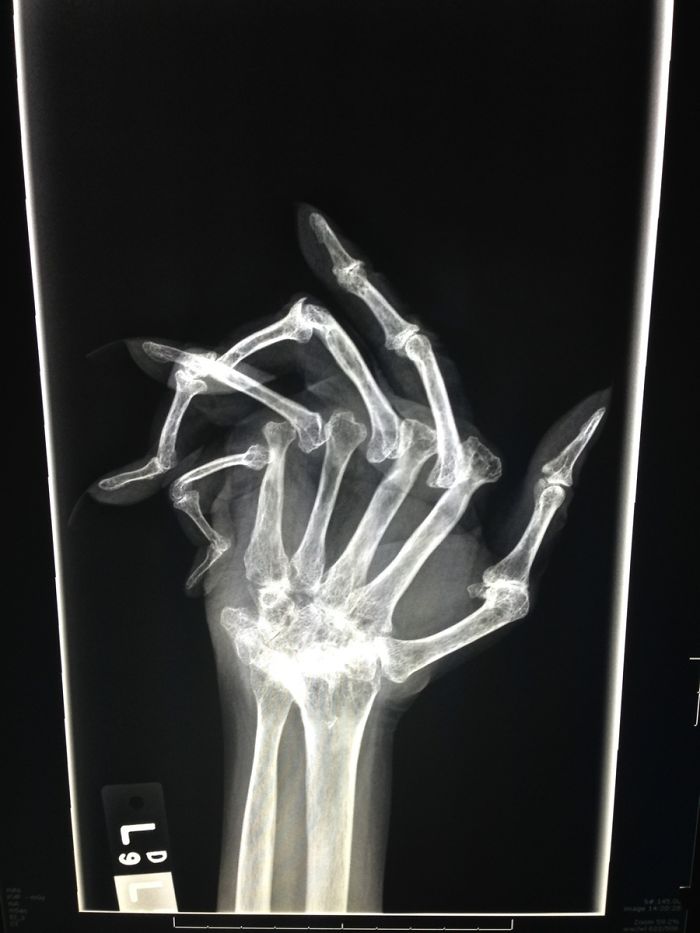

Так выглядит прогрессирующий ревматоидный артрит